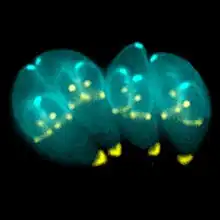

Complejo apical

El complejo apical (api-complex en inglés) de T. gondii, es un conjunto complejo de elementos estructurales y secretores en el extremo apical del parásito adulto, que se construye sobre un conjunto de fibras dispuestas en espiral alrededor del conoide. Este complejo tiene también tres unidades de membrana (como se ve en el esquema C): una membrana plasmática externa (en negro) y dos membranas en el complejo de membrana interna (IMC en rojo) que son las paredes de vesículas aplanadas (sacos alveolares).[6]

El complejo apical proporciona un marco semirrígido para las células puntiagudas de T. gondii y es el destino para los orgánulos secretores, que liberan varios factores de invasión.[7]

El complejo apical se organiza alrededor de un anillo polar apical (APR en inglés), que sirve como centro organizador y nuclea una serie de microtúbulos, que descienden hacia la parte posterior de la célula.

Además de su estructura, el complejo apical actúa como un centro de señalización, al ser el punto de convergencia de muchas vías reguladoras.[8]

Conoide

El conoide de T. gondii, está formado por un conjunto compacto de fibras de citoesqueleto dispuestas en espiral, que se mueven activamente durante la etapa de invasión de las células del huésped.

Las estructuras asociadas con el conoide son: los anillos pre-conoidales, en la punta distal del conoide, donde se originan las fibras conoides; el anillo polar, del que se originan 22 microtúbulos (MT) sub-peliculares; y dos MT intra-conoidales cortos, que pueden utilizarse como vías para el transporte de vesículas secretoras esenciales para la invasión.[6]

T. gondii también posee orgánulos secretores especializados: las micronemas (M), las roptrías (R) y los gránulos densos (DG). La secreción en secuencia de estos tres tipos de orgánulos secretores dirigen tanto la entrada en la célula huésped, como la formación de la PV.[9]

Algunos de los orgánulos que pueden ser encontrados en la imagen de microscopía electrónica de la derecha son:

apicoplasto (A); anillo polar apical (APR); conoide (C); anillo conoidal (CR); aparato de Golgi (G); complejo de membrana interna (IMC); Micronemas (M); mitocondria (Mi); microtúbulos (Mt); núcleo (Nu); roptrias (R); conducto de roptria (RD); vacuola (V).